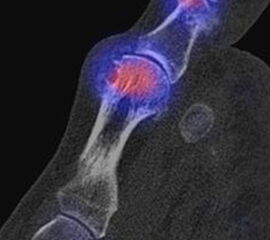

Bekannte Gicht mit Polyarthralgien. Am rechten Großzehengrundgelenk lateral in der Grundphalanx entzündliche Erosionen.

Zum Lesen der Bildbeschreibung und zur Vollansicht bitte das Bild anklicken. Bild: H. C. Rischke